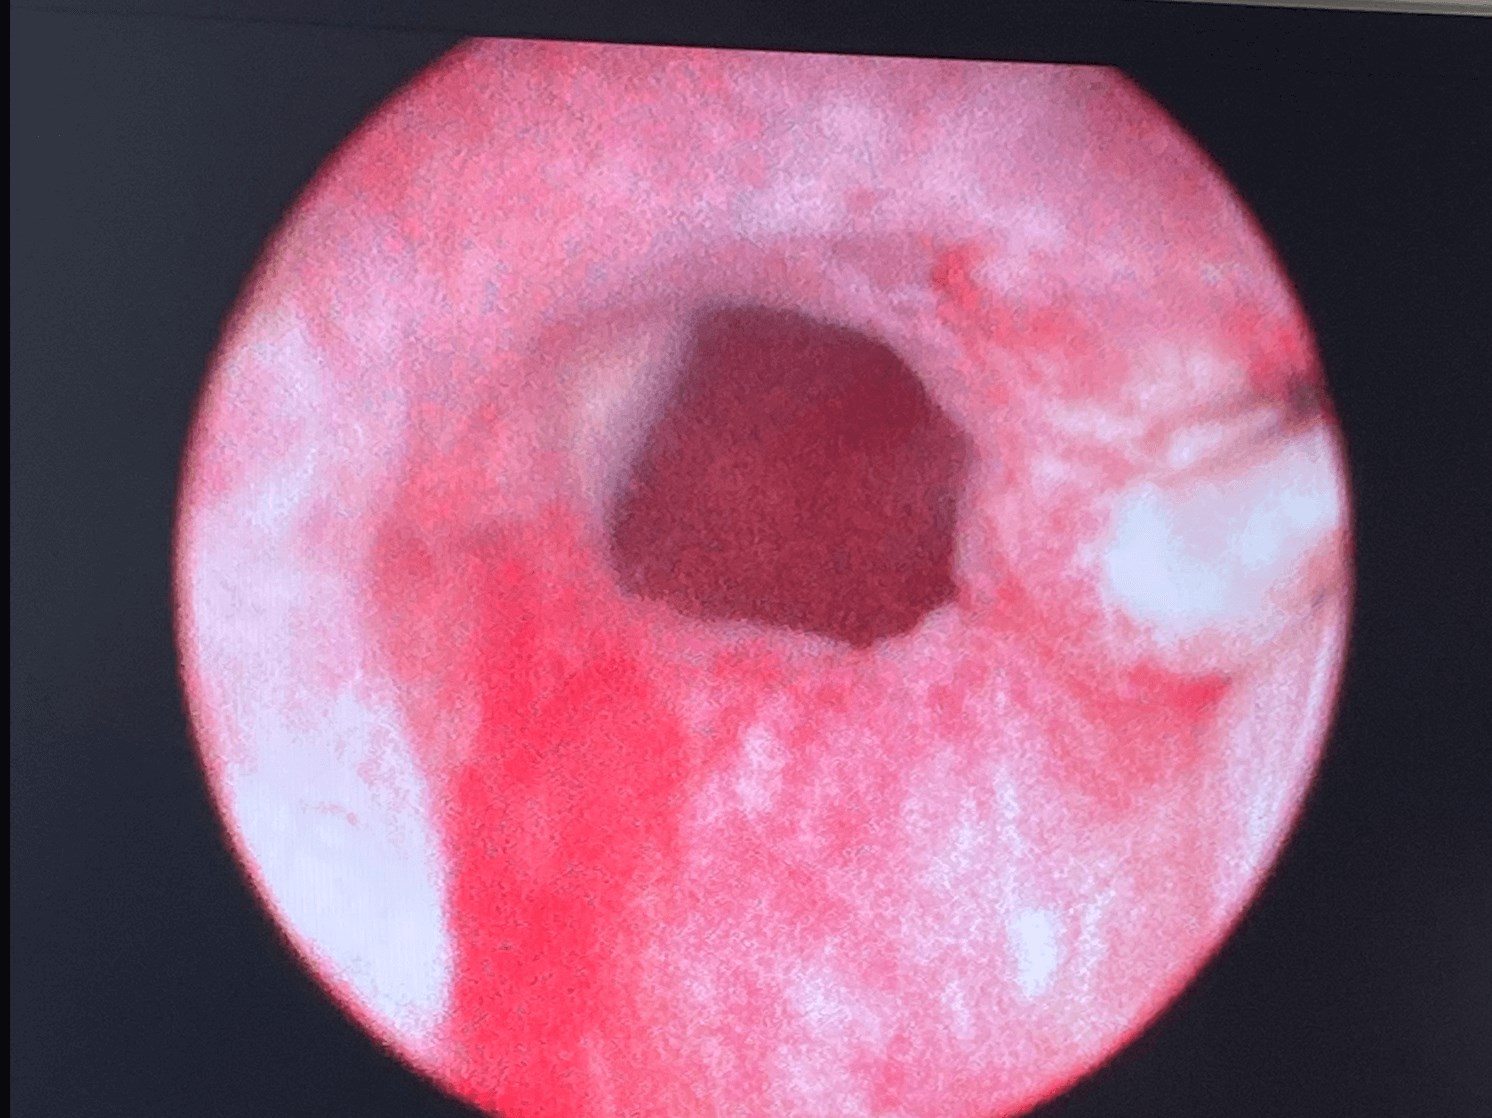

Patient had complications with ejaculating before Urolift

Procedure